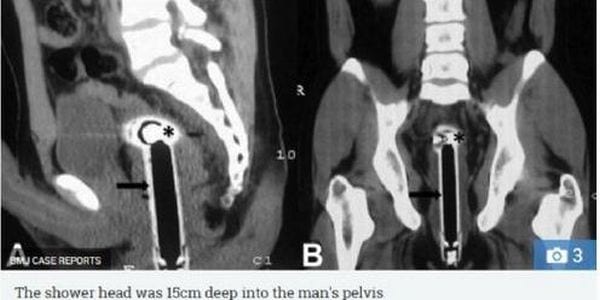

L’uomo ha affermato di essere caduto nella doccia e che parte del tubo era rimasto incastrato nel suo retto. Il medico che lo ha soccorso ha scritto una lettera al British Medical Journal per raccontare il fatto e sensibilizzare l’opinione pubblica su un tema che solitamente suscita omertà e vergogna. “Sto davvero facendo fatica a immaginare questa caduta sotto la doccia, per essere onesti. Per il momento darò al ragazzo il beneficio del dubbio. È un argomento troppo delicato per molti pazienti”, ha affermato il dottor Peeyush Kumar. Il paziente, non riuscendo ad estrarre il soffione della doccia dal corpo, per potersi recare al pronto soccorso ha dovuto staccare il tubo dalla parete della sua abitazione. Per fortuna non c’era alcun sanguinamento o infezione in corso, sebbene sia stato necessario un delicato intervento per rimuovere il corpo estraneo che era arrivato addirittura a perforare l’intestino. Il dottor Kumar ha potuto aiutarlo e permettergli di tornare alla sua vita nel giro di 48 ore, ma non ha fatto cadere la questione nel dimenticatoio.